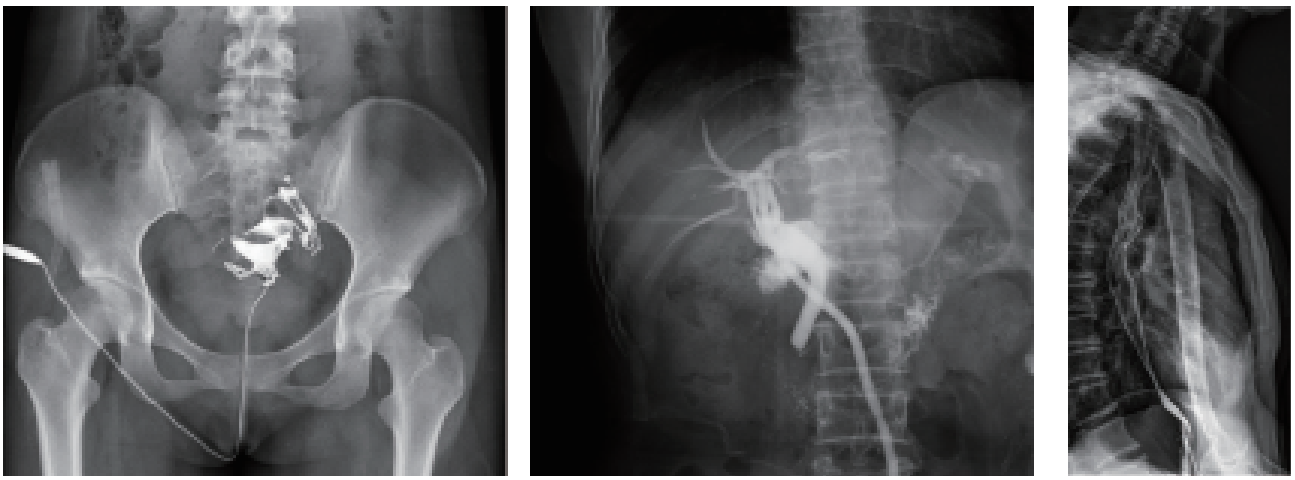

数字化造影:

泌尿造影、膀胱造影、妇科造影、关节造影、胰胆管造影等